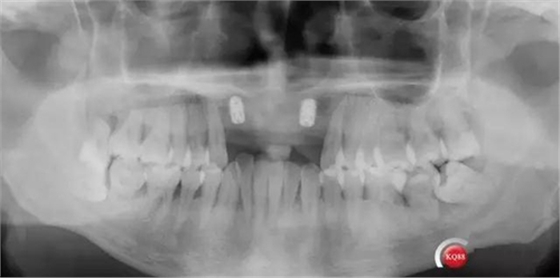

靜靜等待3個(gè)月全景,未見(jiàn)異常